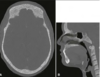

What are these radiographic findings?

Residual Cysts

What is the radiographic finding?

Residual Cyst

Residual Cyst

Radigraphically

- well defined round to oval radiolucency in the site of a previous extraction